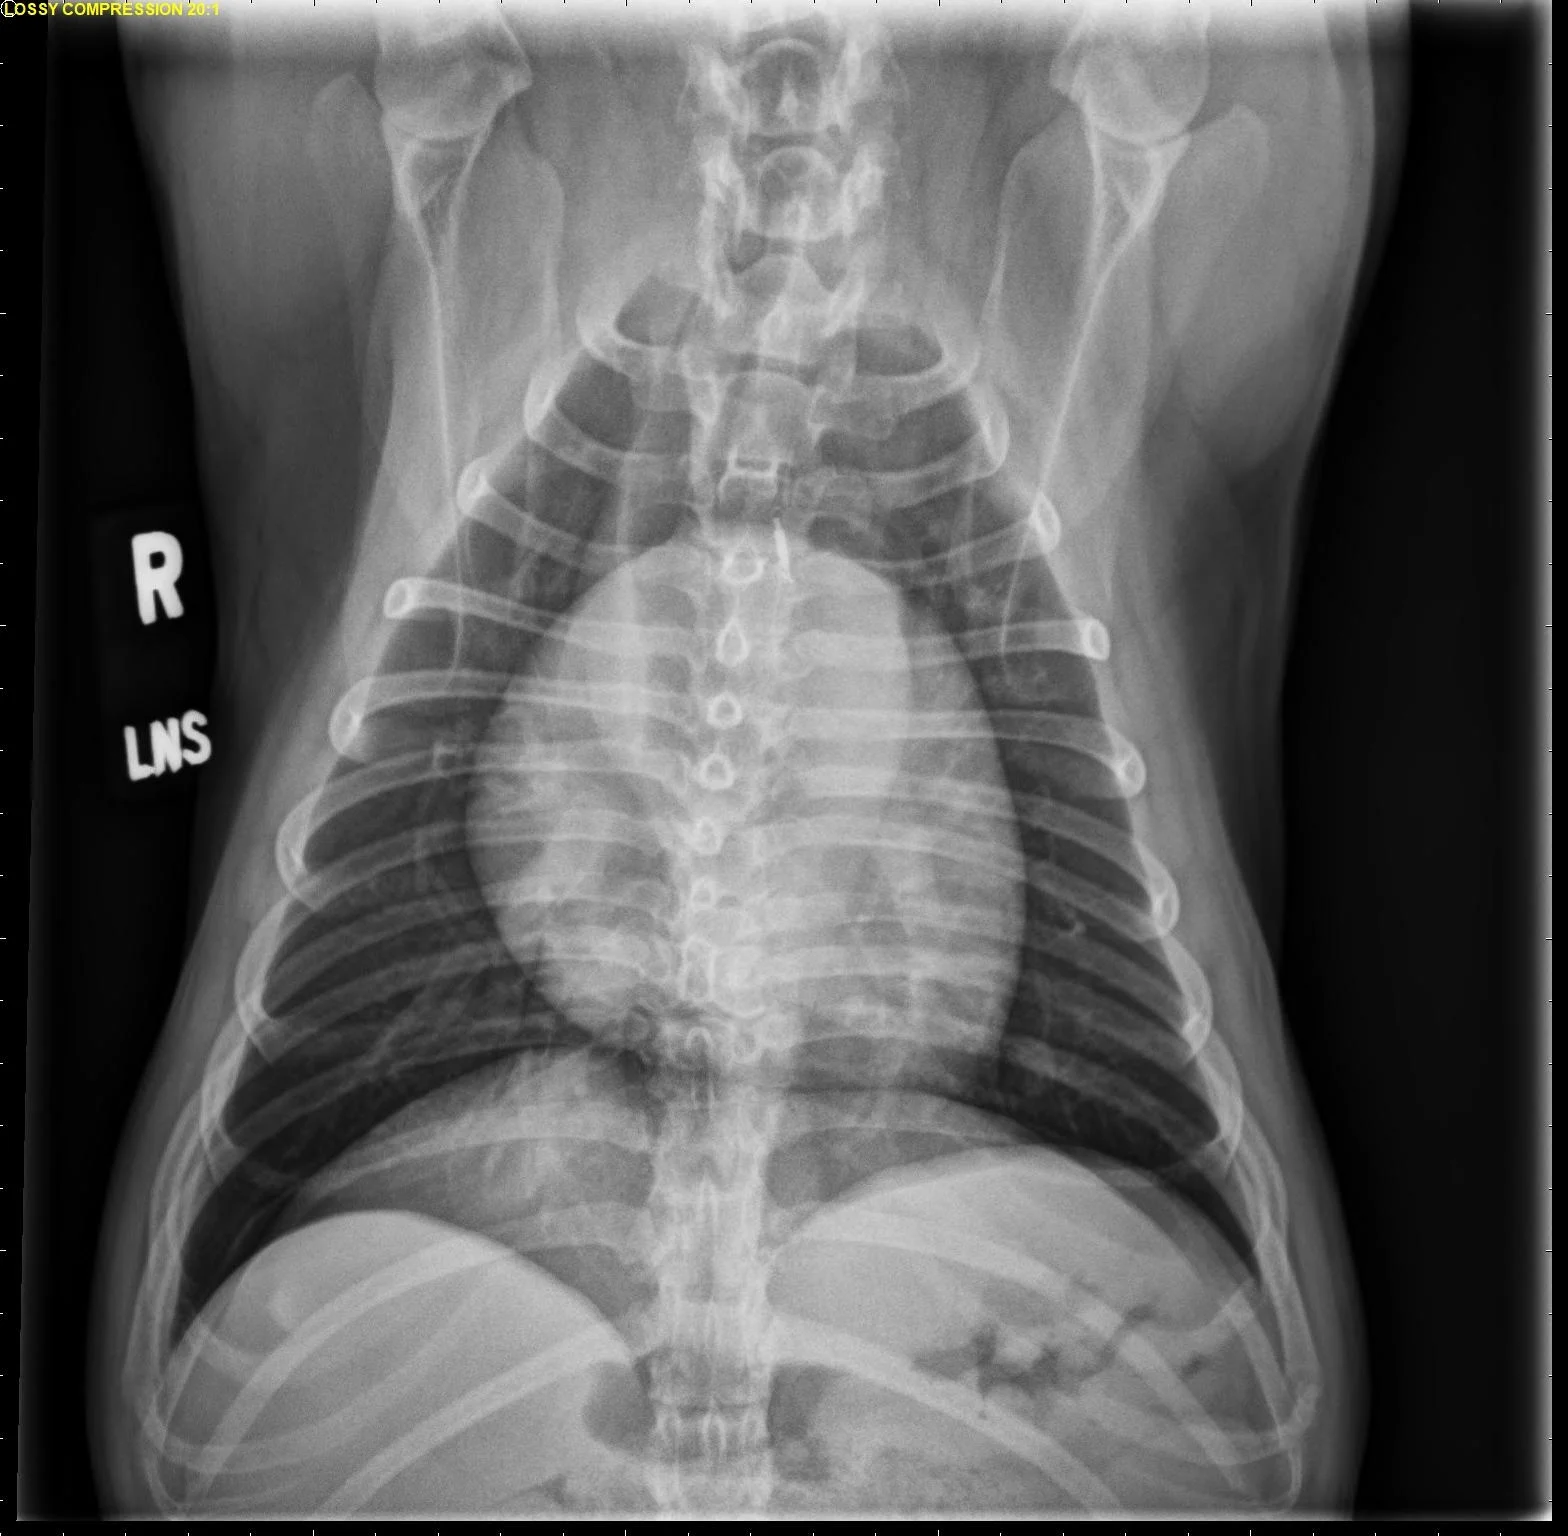

The size of the cardiac silhouette relative to the thoracic cavity can vary significantly among breeds and in patients with different BCS. This finding is supported by variation of the normal range of vertebral heart scale (VHS) among breeds.1-3 In general, deep-chested dogs have an elongated heart and a lower VHS than brachycephalic breeds, which typically have a wide cardiac silhouette and a higher VHS normal range (Figure 3).

FIGURE 3 Normal VD (A), right lateral (B), and left lateral projections (C) in an English bulldog. The increased size of the cardiac silhouette relative to the thorax in this patient versus the patient in Figure 1 is evident. VHS, VLAS, M-VLAS, and VRHi collected from the right lateral view are 13.9, 2.4, 2.9, and 4.2, respectively, and 14, 2.2, 2.7, and 4.4, respectively, collected from the left lateral view. Images courtesy of Federico Villaplana Grosso, DACVR, DECVR